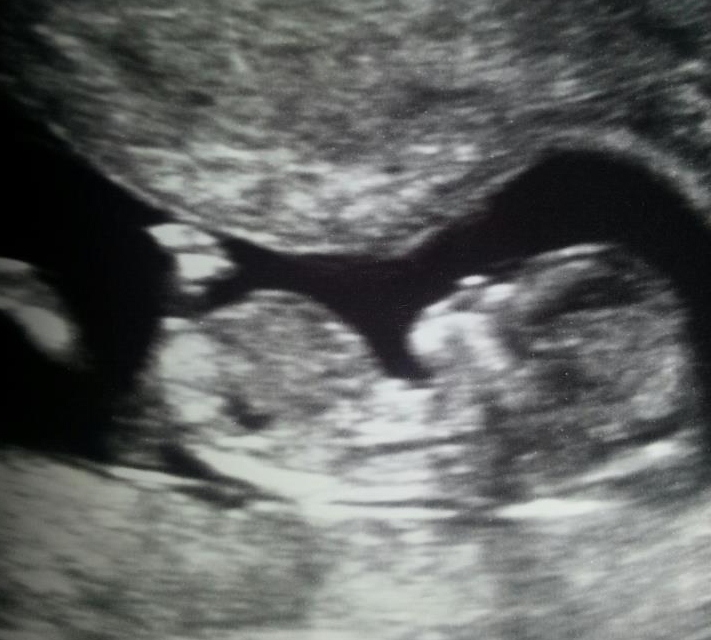

Hi ladies i have attached my sister in law's 12 week ultrasound pic and she would love it if you could give her a gender guess.

I do t see a nub and if what I am seeing is the nub it's very short and stubby which would make me lean boy

No nub in this image--it cuts off at the end of baby's tummy so that area isn't even included.